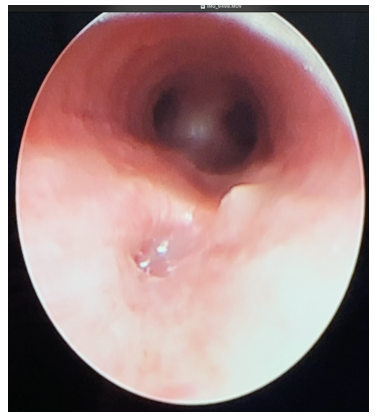

Abdominal radiographs showed persistent severe distension of the gastric chamber despite high caliber tube drainage and evidence on one occasion of bubbling of the same so tracheoesophageal fistula was suspected. Barium esophagogram was performed with evidence of complete passage into esophagus, stomach and pylorus, without a fistulous tract (Figure 1). However, due to persistent symptoms, bronchoscopy was performed to rule out congenital malformation of the airway, H-type tracheoesophageal fistula of 3 mm in diameter located 5 rings above the carina was visualized, nevertheless, endoscopic or surgical correction at this time was not possible due to hemodynamic instability (Figure 2).

Figure 2 Bronchoscopy: 3 mm diameter tracheoesophageal H-fistula located 5 rings above the carina.